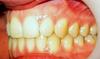

!Мне орт про мой прикус ни чего совсем не говорила, все как то о зубах. Я даже не знаю в норме он у меня или нет. Смотрю в альбомах, у многих такие уже красивые, ровные зубки, а носить еще долго,что-то с прикусом. Читала в инете про него, все равно ни чего не пойму. Поняла когда ВЧ выступает сильно над НЧ, поняла что НЧ может выступать. А ведь (еще раз повторюсь) у многих с этим все нормально. В общем совсем я запуталась

Пыталась пойти от обратного, найти фотку с идеальным прикусом, но тоже как то не повезло

хах,картиночка класс,хоть на выставку отправляй!!!!!!хочу такой прикус!!!!!!

на картинке прямо прикус-мечта...

Неправильный это когда НЧ впереди, ВЧ впереди, т.е. стоит неправильно от установленой нормы. В норме ВЧ должна перекрывать НЧ чуть меньше половины, и не должно быть промежутков, когда рот закрыт